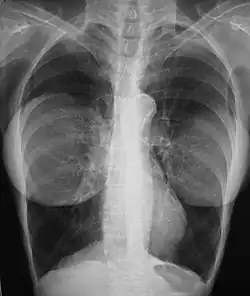

Mammography

The presence of radiologically opaque breast implants (either saline or silicone) might interfere with the radiographic sensitivity of the mammograph, that is, the image might not show any tumor(s) present. In this case, an Eklund view mammogram is required to ascertain either the presence or the absence of a cancerous tumor, wherein the breast implant is manually displaced against the chest wall and the breast is pulled forward, so that the mammograph can visualize a greater volume of the internal tissues; nonetheless, approximately one-third of the breast tissue remains inadequately visualized, resulting in an increased incidence of mammograms with false-negative results.[119][120]

The breast cancer studies Cancer in the Augmented Breast: Diagnosis and Prognosis (1993) and Breast Cancer after Augmentation Mammoplasty (2001) of women with breast implant prostheses reported no significant differences in disease-stage at the time of the diagnosis of cancer; prognoses are similar in both groups of women, with augmented patients at a lower risk for subsequent cancer recurrence or death.[121][122] Conversely, the use of implants for breast reconstruction after breast cancer mastectomy appears to have no negative effect upon the incidence of cancer-related death.[123] That patients with breast implants are more often diagnosed with palpable—but not larger—tumors indicates that equal-sized tumors might be more readily palpated in augmented patients, which might compensate for the impaired mammogram images.[124] The ready palpability of the breast-cancer tumor(s) is consequent to breast tissue thinning by compression, innately in smaller breasts a priori (because they have lesser tissue volumes), and that the implant serves as a radio-opaque base against which a cancerous tumor can be differentiated.[125]

The breast implant has no clinical bearing upon lumpectomy breast-conservation surgery for women who developed breast cancer after the implantation procedure, nor does the breast implant interfere with external beam radiation treatments (XRT); moreover, the post-treatment incidence of breast-tissue fibrosis is common, and thus a consequent increased rate of capsular contracture.[126] There is tentative evidence that women who have had breast augmentation, have worse breast cancer prognosis.[127] The use of implants for breast reconstruction after breast cancer mastectomy appears to have no negative effect upon cancer-related death.[123][128]

There have been multiple reported cases of other adverse effects of mammography of women with breast implants; ruptures resulting from pressure exerted on the breast implant make up a majority of these cases.[129] Compression may also lead to pain or exacerbate already existing pain in the breasts.[129]